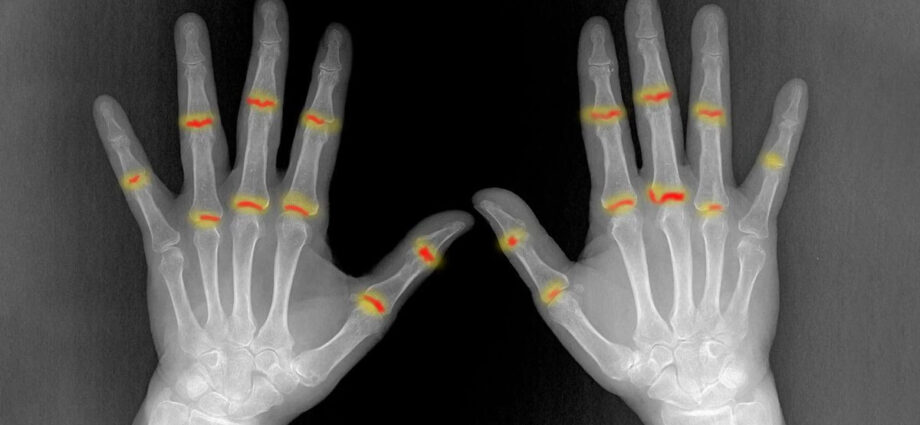

Για πολλά χρόνια η επιστημονική κοινότητα γνώριζε ότι η ψωρίαση δεν περιορίζεται μόνο στην επιφάνεια του δέρματος. Ένα σημαντικό ποσοστό ασθενών, περίπου το 30%, αναπτύσσει τελικά ψωριασική αρθρίτιδα, μια επώδυνη και συχνά μη αναστρέψιμη φλεγμονώδη πάθηση. Το ερώτημα που παρέμενε αναπάντητο, ωστόσο, ήταν το «γιατί». Γιατί ορισμένοι ασθενείς εμφανίζουν αρθρίτιδα ενώ άλλοι όχι; Και πώς ακριβώς μεταδίδεται η φλεγμονή από το δέρμα στις αρθρώσεις;

Μια νέα μελέτη από το Πανεπιστήμιο Friedrich-Alexander-Universität Erlangen-Nürnberg (FAU) ρίχνει φως σε αυτόν τον μηχανισμό, αποκαλύπτοντας μια αθέατη διαδρομή κυττάρων και μια κρίσιμη αποτυχία του αμυντικού συστήματος των αρθρώσεων.